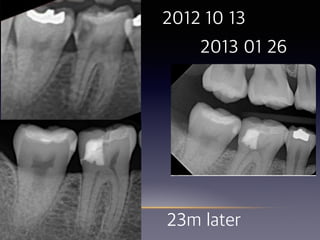

#30 Partial pulpotomy

(23 female)

2013 01 26

2012 10 13

23m later

26

21m later